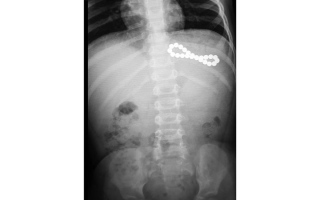

«الكرات المغناطيسية» تهدد حياة الصغار بتلف الأمعاء.. و114 ابتلعوها خلال 10 سنوات